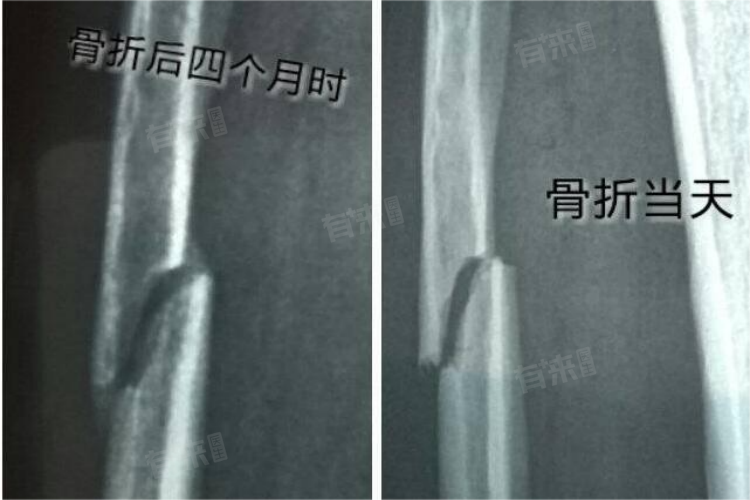

骨折线模糊是骨折愈合过程中的一种常见现象,通常表示骨折处正在愈合。其并不直接等同于骨折完全愈合,也不代表完全不会出现骨不连的情况。

- 骨折线模糊通常出现在X光或CT检查中,表现为骨折部位的影像变得不清晰。这一现象通常意味着骨折处的骨质开始愈合,骨折边缘的骨痂正在形成,骨折断端的稳定性逐渐增强。